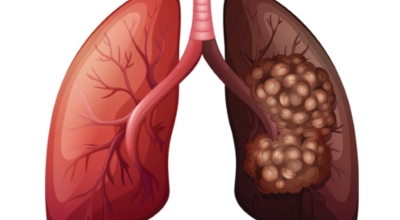

최근 슈퍼푸드로 떠오르고 있는 적양파는 알리신 물질이 매우 많은데요, 이는 항염, 항균, 항산화에 대단한 물질이 많이 들어있어 폐 건강에 도움을 주는 채소입니다. 양파에 들어있는 퀘르세틴 성분 역시 항산화 역할을 하고 세포 훼손을 예방하므로 폐에 생기게 될 수 있는 염증, 폐암도 미리 막을 수 있습니다.

케일은 가지가지 매체에서 체중 감량로 저명한 음식이죠. 페놀과 플라보노이드라는 물질이 폐암을 예방에 큰 보탬이 되기도 합니다. 다른 채소들에 대조해 유해한 물질을 미리 막는 역할이 뛰어나서 흡연자분들이 계신다면 케일을 갈아 빈번히 마셔주면 좋습니다. 쓴맛이 나기 때문에 케일만 갈아서 먹기 힘들다면 사과와 같은 맑은 즙을 내는 과일과 함께 갈아드시면 더욱더 마시기가 좋답니다.

비트에는 매우 많은 항산화 성분을 함유하고 있답니다. 마그네슘, 칼륨, 비타민C와 카로노이드과 같은 산화를 억제하는 물질는 폐의 염증을 완화해주는 효과가 있으며, 천식이나 기침, 폐렴을 예방에 도움 됩니다. 보통과 다르게 비트에 풍성하게 함유되어있는 베타인이라고 부르는 물질은 암세포를 사멸하는 역할을 하는데 한 연구에 근거하면 베타인을 많이 먹은 그룹의 폐암 발병률이 30%이상 낮아지는것으로 확인되었습니다.